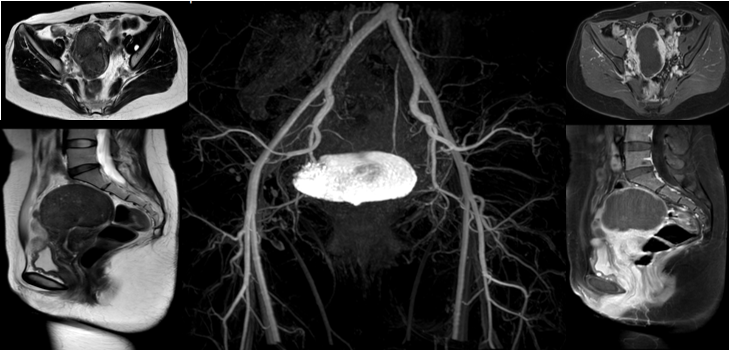

治疗过后3个月来例假,月经量很少,胡女士发现痛经消失了,胡女士不敢相信困扰她多年的痛经竟然这样消失了,她还有些不敢相信。虽然出院时韦文姜副主任医师告诉她治疗后三个月复查,但胡女士想再观察几个例假周期看看痛经是不是真的好了。这样一观察就1年多,痛经和呕吐没有再出现,治疗后16个月胡女士回门诊复查磁共振显示:子宫腺肌病病灶坏死无强化,较治疗前病灶明显缩小(如下图)。